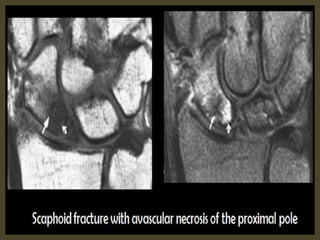

Scaphoid waist fracture with subtle collapse of the proximal pole, related AVN .

Diffuse enhancement of scaphoid proximal pole has good correlation

with stage group I, patchy enhancement have correlation with

grade II and III and enhancement with complete necrosis.